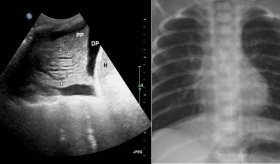

De acuerdo con el portal Mayo Clinic, el cáncer de esófago se refiere a la proliferación anormal de células en el esófago, un conducto largo y hueco que conecta la garganta con el estómago, facilitando el paso de los alimentos. Este tipo de cáncer generalmente comienza en las células que recubren el interior del esófago, aunque puede desarrollarse en cualquier parte del mismo. Es más común en los hombres y el consumo de alcohol y tabaco son factores de riesgo conocidos.

El tratamiento para el cáncer de esófago suele implicar una intervención quirúrgica para extirpar el tumor. Además, pueden emplearse otros tratamientos como la quimioterapia, la radioterapia o una combinación de ambos. En algunos casos, se recurren a terapias dirigidas o a la inmunoterapia.

El cáncer de esófago puede no presentar síntomas en sus primeras etapas. Los signos de la enfermedad suelen aparecer cuando ya está avanzada.